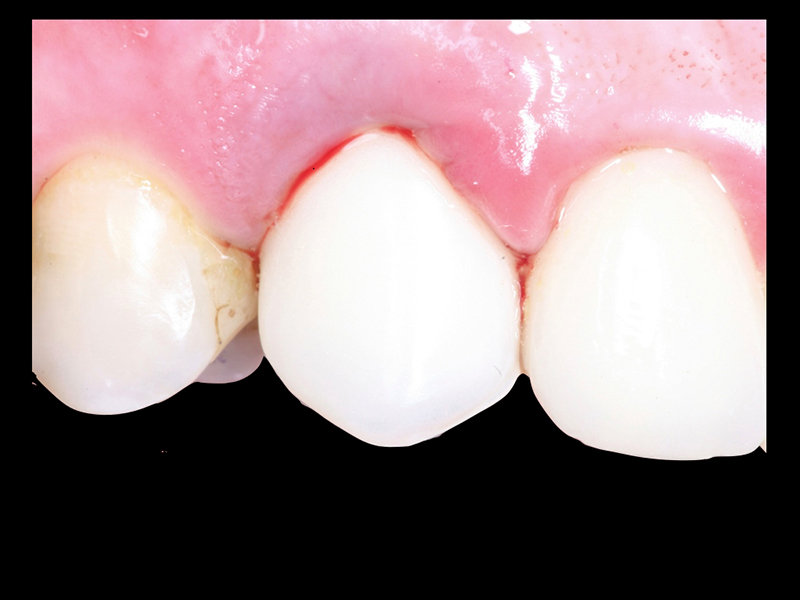

- Planejamento Digital: Com o auxílio de tecnologias como tomografias e softwares 3D, a posição dos implantes é planejada com precisão.

- Cirurgia de Instalação dos Implantes: Os implantes são fixados no osso maxilar ou mandibular, proporcionando uma base sólida para a prótese.

- Fixação da Prótese: Em até 72 horas após a cirurgia, a prótese provisória é instalada, permitindo que o paciente recupere a funcionalidade e a estética imediatamente.

Tecnologia e Especialização: O diferencial da Clínica Pontes Odontologia